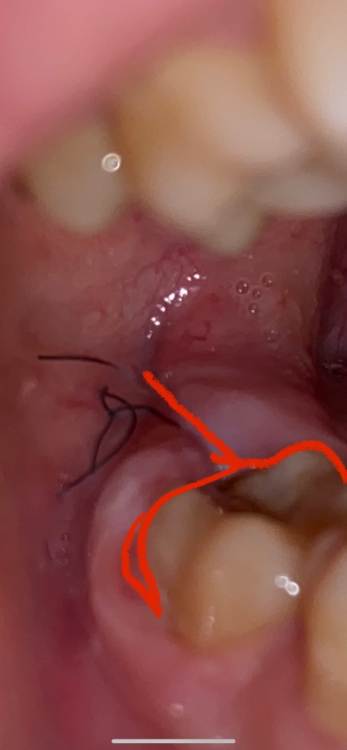

Karina21 Опубликовано 30 июля, 2021 Автор Поделиться Опубликовано 30 июля, 2021 @Irouil @Karina21 полоскать сказали и дома физраствором вдоль этих линий. Десна легко отодвигается в местах, которые отметила красным маркером начиная от середины 7 зуба. Сегодня промыли и положили альвожил, сейчас не болит вообще, но я не понимаю процесс заживления, если постоянно промывать, десна разве не будет просто болтаться потом? Ведь рану раскрывать почти как книгу(чтобы промыть) приходится вот типа как над восьмым зубом сверху капюшон из десны бывает и десна не герметично над зубом находится Ссылка на комментарий